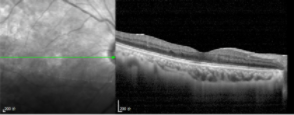

正常OCT图

OCT检查可见明显的黄斑水肿